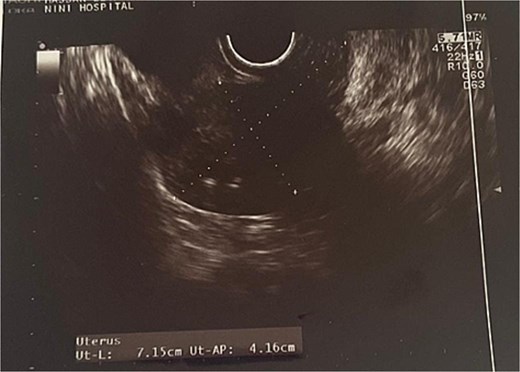

Transvaginal ultrasound revealed a well-circumscribed, heterogeneous uterine mass with mixed echogenicity (Figs 1 and 2). Given the imaging characteristics, a malignant uterine neoplasm, particularly sarcoma, was initially suspected.